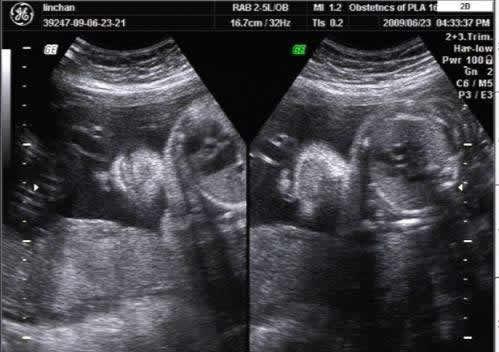

随着医疗技术的不断发展,孕妇在怀孕期间做产检是必备的过程。4维彩超的出现更是成为了不少孕妈妈产检的首要选择,那么问题来了,产检必须做4维彩超吗?4维彩超到底检查什么呢?这个问题据说80%的妈妈都不知道!

首先产检四维彩超不是必须做的,完全自愿。四维彩超可以拍到宝宝的大致轮廓,或许可以帮助你辨别宝宝的性别。而且可以保存下来,当成是孩子的第一份礼物。但成像的前提是宝宝必须是正面且面部无遮挡,这种几率基本上是百分之五十吧,有时候需要碰碰运气。

四维彩超不再是仅仅感觉宝宝的呼吸和运动,而是可以亲眼目睹他们的一举一动和乖巧的秀容。更为重要的是,四维彩超能够多方位、多角度地视察宫内胎儿的生长发育情况,为早期诊断胎儿先天性体表畸形和先天性心脏疾病提供准确的科学依据。